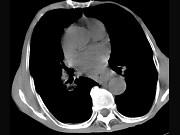

问题 女,71岁,进食时有梗阻感,进行性加重半年,影像检查如图,最可能的诊断是()

选项 A.贲门失弛缓症 B.食道癌并纵隔淋巴结转移 C.食道良性狭窄 D.返流性食道炎 E.食道静脉曲张

答案 B